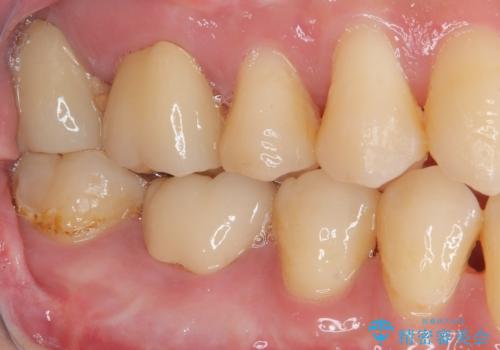

上顎は仮歯に置き換えた後に、それまでの痛みは一切感じなくなり、下顎も一度目の根管治療で痛みを感じることはなくなりました。

根管治療を行った歯の周辺にある病変は数ヶ月後にレントゲン写真を撮って確認する必要があるため、今後経過観察を行っていく予定です。